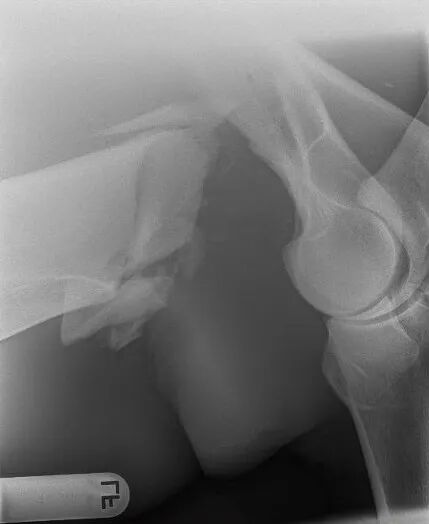

一匹马在麻醉苏醒过程中发生肱骨粉碎性骨折